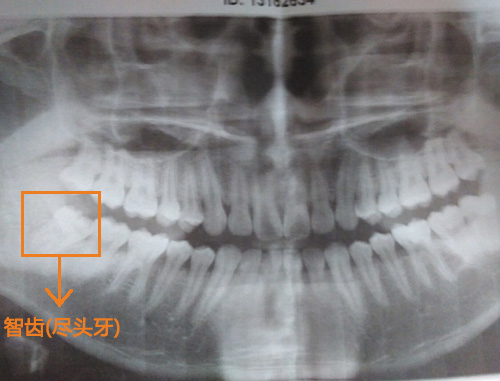

智齒也被稱為盡頭牙,大多數(shù)人是在18歲以后才逐漸長出來。智齒本屬于大牙,應該承擔堅硬食物的咀嚼功能,但由于人類在進化過程中,食物越來越精細,牙槽骨發(fā)育逐漸退化,留給智齒的宅基地越來越小,因此許多人在智齒生長的過程中很容易出現(xiàn)異常,而常見的就是牙齦腫痛,疼痛難忍。

醫(yī)生答:一般智齒沒有咀嚼功能或位置不正,都是建議拔除的。您這顆屬于高位阻生,如果不拔除,讓其繼續(xù)生長是會影響旁邊牙齒的。而且現(xiàn)在也已經(jīng)有癥狀了,是建議拔除的。